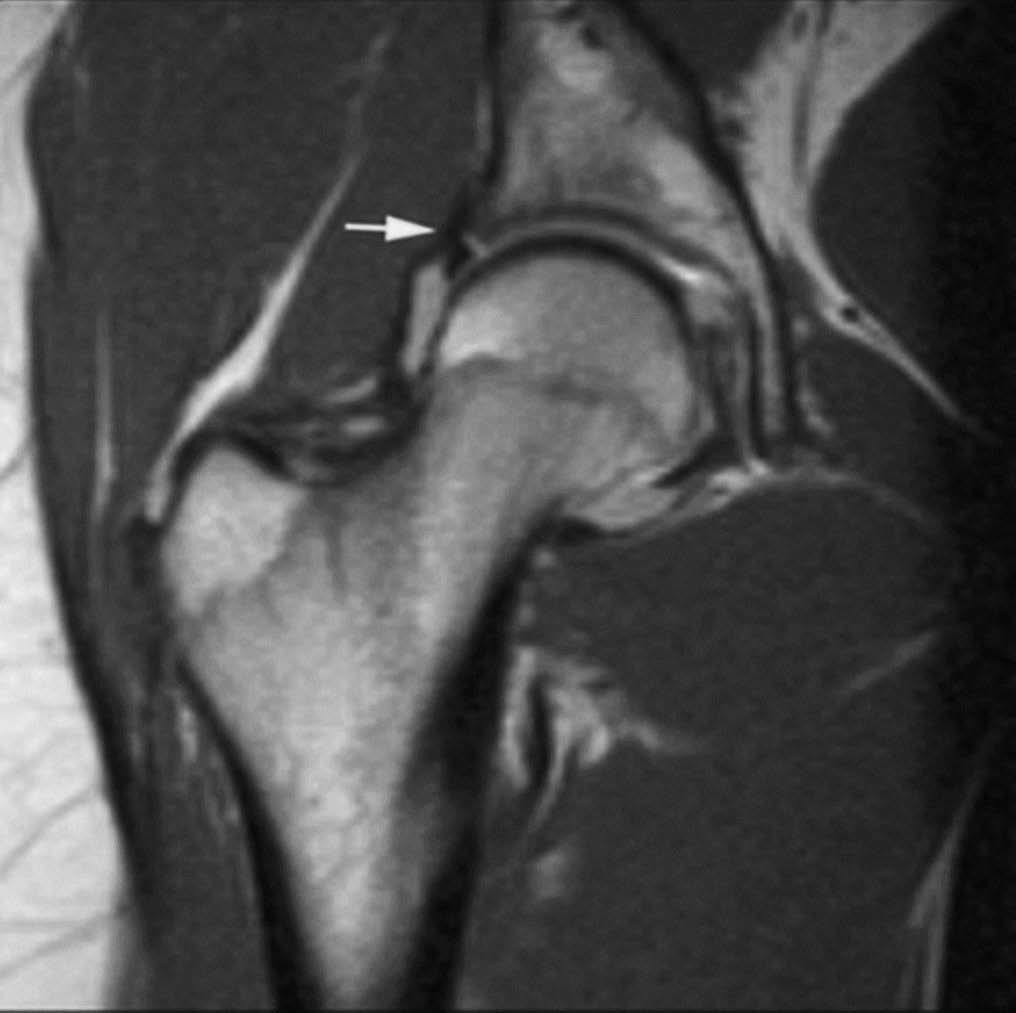

Las roturas ocurren generalmente en el labrum antero-superior (fig. 2) y pueden asociarse a la formación de quistes paralabrales o subcondrales que pueden comunicar o no con la superficie articular en el estudio de RMA. Las secuencias T2 son fundamentales para demostrar estos quistes. El contorno labral es generalmente liso en las imágenes de RMA, aunque pueden mostrarse ligeras irregularidades del margen libre y pequeños surcos en su unión con el cartílago articular1-3,6.

Fig. 2.--Rotura traumática del labrum antero-superior. A) Corte coronal oblicuo de RMA potenciado en T1. B) Corte sagital oblicuo de RMA potenciado en T1. Se observa un desgarro lineal en la base del labrum antero-superior (flechas).